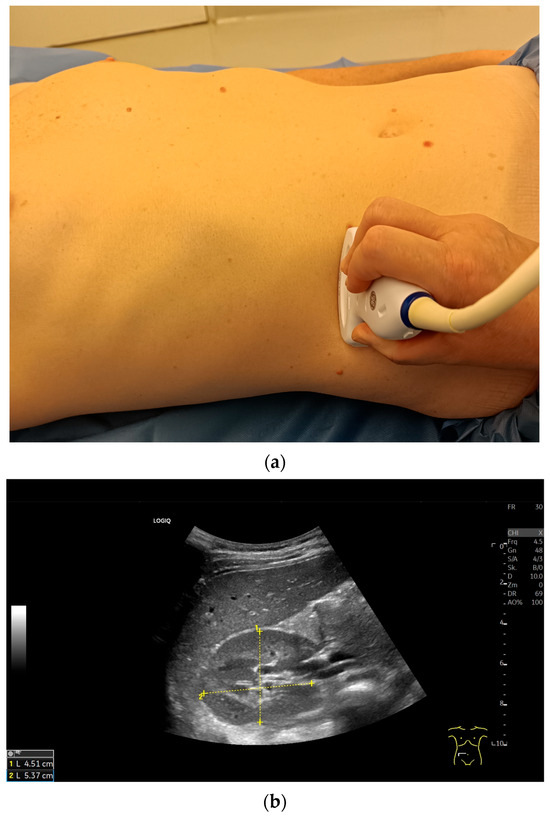

Variability of Renal Ultrasound Measurements: How Physician Experience and Patient Position Affect Measurement Accuracy?

This study was designed to investigate the variability of renal ultrasound measurements, focusing on the impact of physician experience and patient position. Background: Since decreased kidney length is considered an indicator for chronic renal disease, understanding measurement repeatability and reproducibility is crucial [...] Read more.

This study was designed to investigate the variability of renal ultrasound measurements, focusing on the impact of physician experience and patient position. Background: Since decreased kidney length is considered an indicator for chronic renal disease, understanding measurement repeatability and reproducibility is crucial for establishing effective diagnostic guidelines. Methods: Fifty healthy young adults underwent renal ultrasound scans performed by three examiners with varying levels of experience (12 years, 5 years, and 4 weeks). Renal length was measured at the level of the hilum in three patient positions: supine, lateral decubitus, and prone, using a 2–6 MHz convex probe (GE Logiq S8). Results: This study found that examiner experience significantly affected the results of sonographic measurements. However, the Interclass Correlation Coefficient analysis for all examiners demonstrated good reliability in most positions, with the highest values observed for the prone position. Measurements in the lateral decubitus position showed highest values, especially for the most experience examiner. The less experienced sonographers produced more variable results. Conclusions: Standardized patient positioning improves the accuracy and reproducibility of renal ultrasound measurements. The prone position offers a balance of reliability and practicality, especially for less experienced operators. Full article